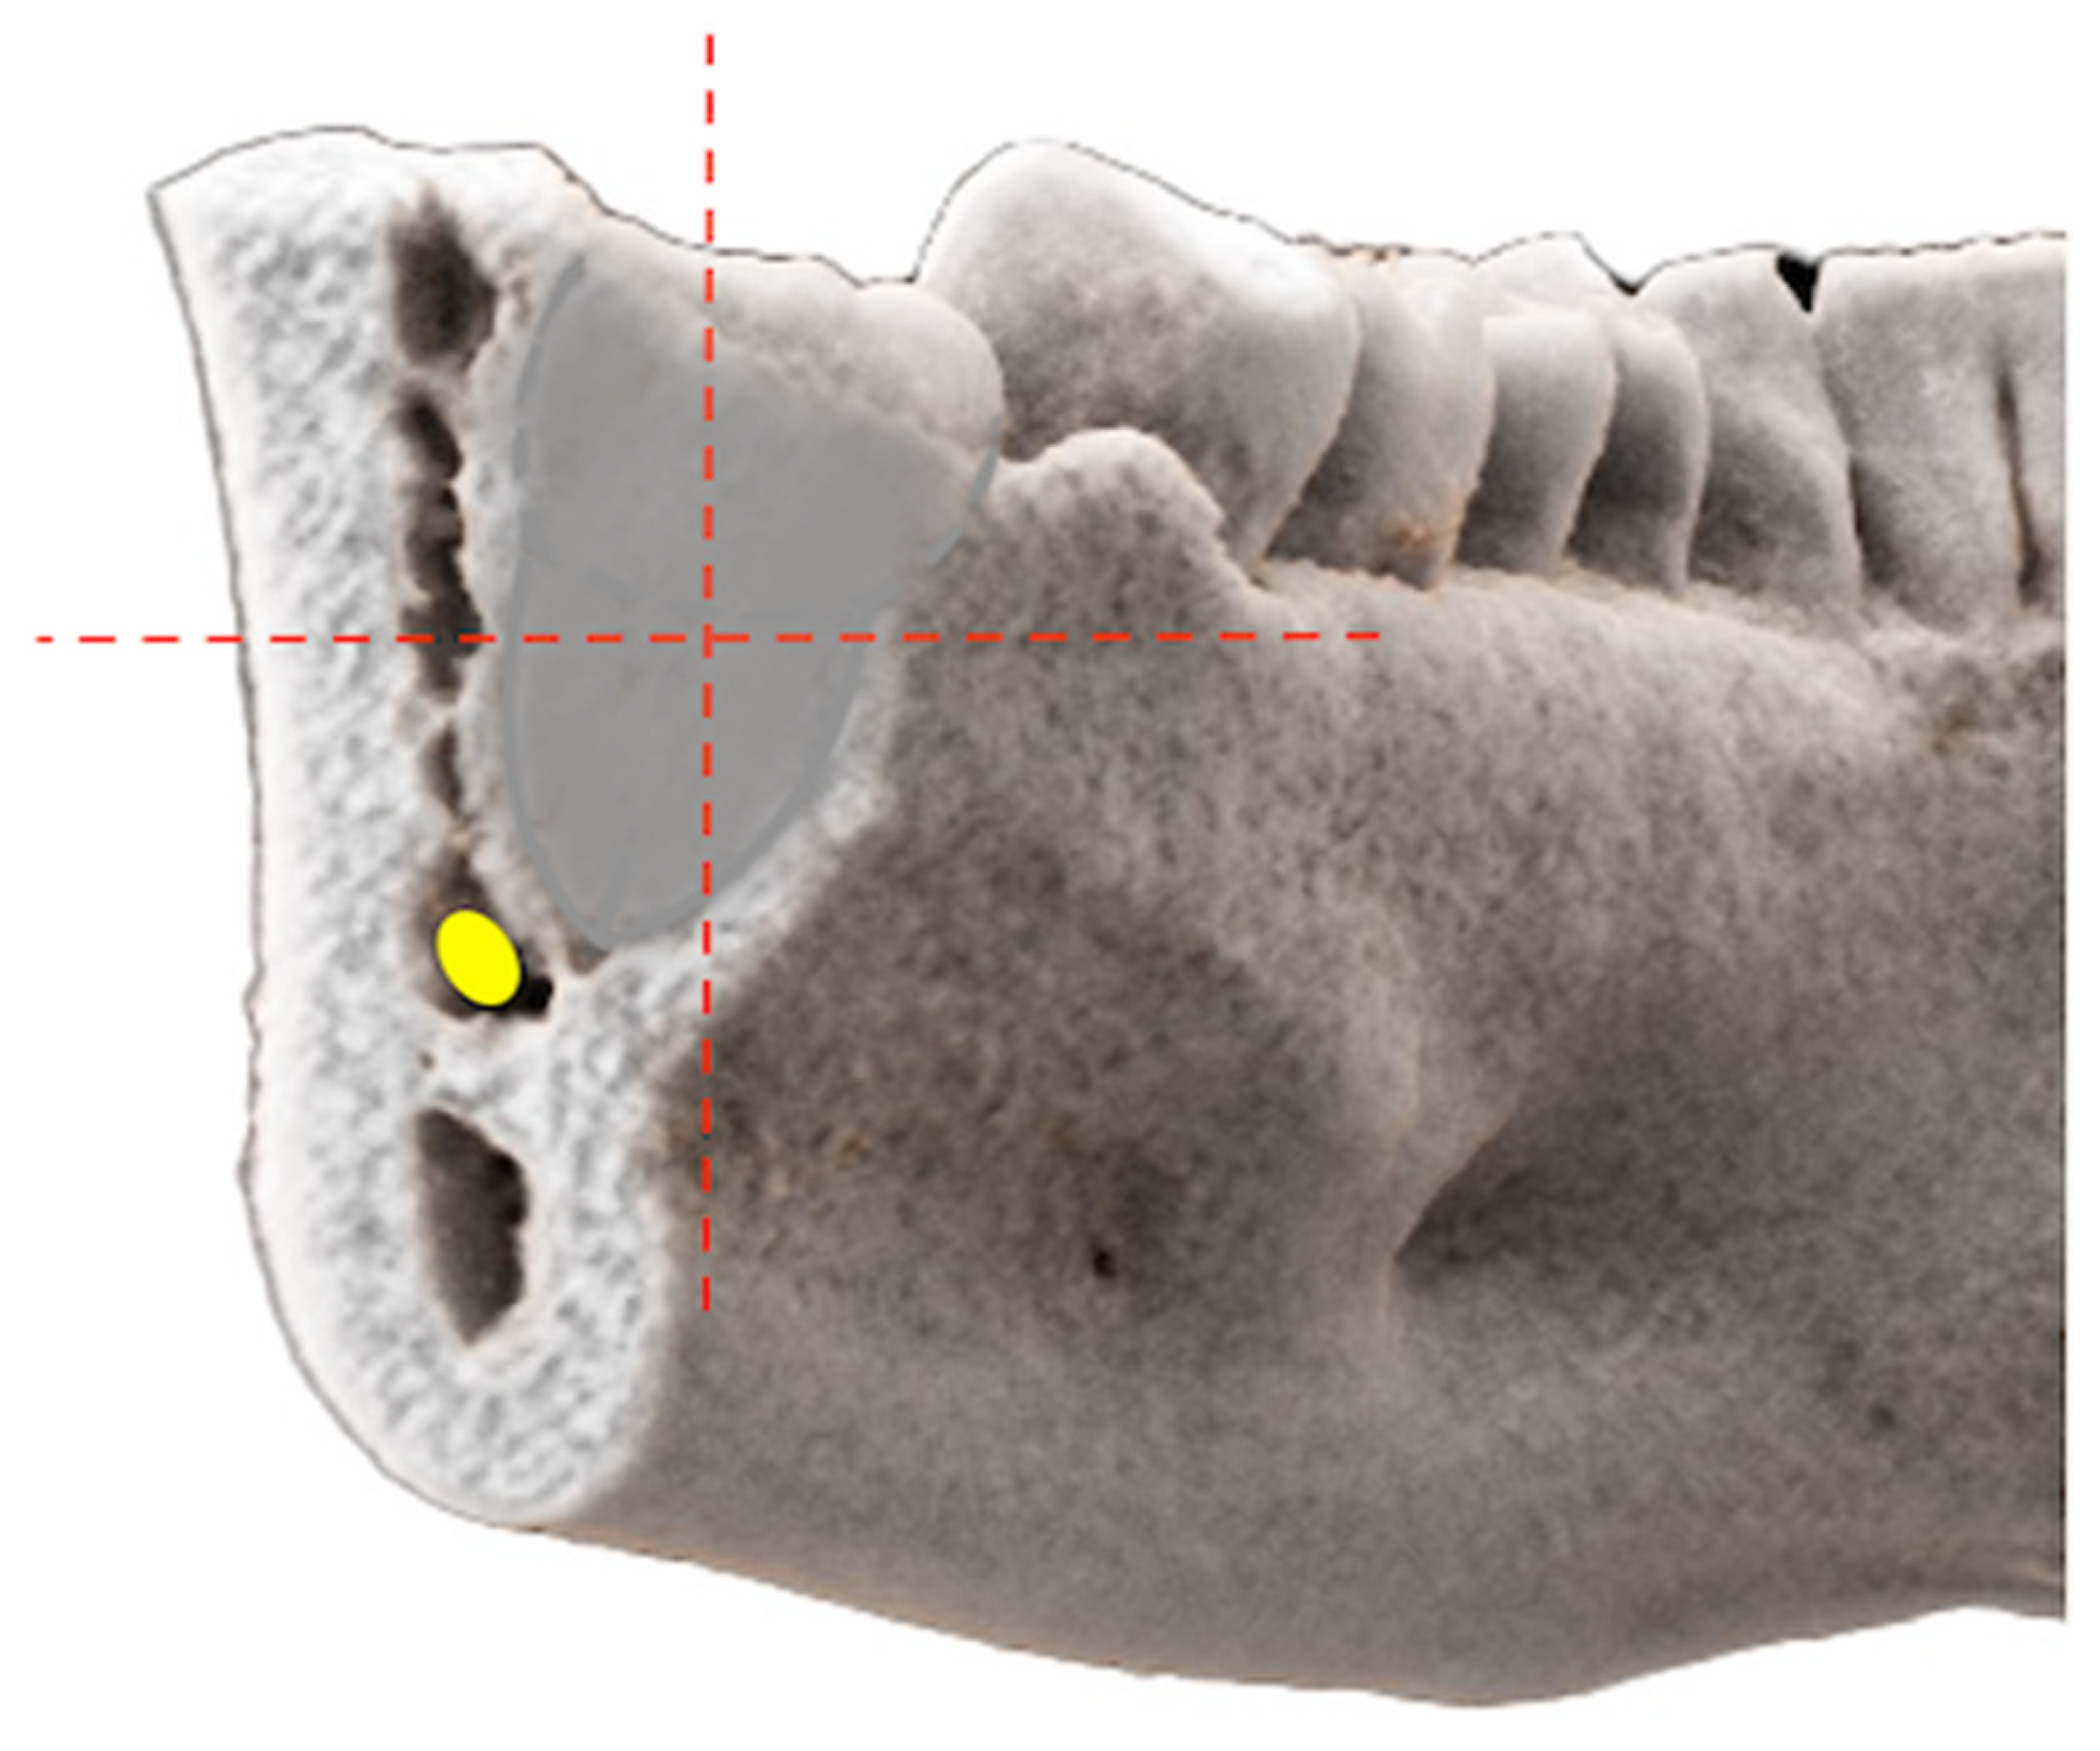

Figure 2. Photorealistic three-dimensional (3D) visualization of a study participant’s cone-beam computed tomography (CBCT) using cinematic rendering (CR) image reconstructions. In the coronal reference layer, showing the closest positional relationship, both readers independently classified the relative positional relationship of the mandibular third molar’s (MTM) roots and the mandibular canal (MC)/inferior alveolar nerve (IAN) by using the Cartesian coordinate system, according to Wang et al. [24] After evaluating whether there was contact or not, the structural center of the MTM was set as the origin in the Cartesian coordinate system and the relative positional relationship—whether the IAN’s position was periradicular (lingual, buccal, inferior) or interradicular (between the roots)—was determined.

In the coronal reference layer, showing the closest positional relationship, both readers independently classified the relative positional relationship of the MTM’s roots and the MC/IAN by using the cartesian coordinate system, according to Wang et al. [24] (Figure 2).

After evaluating whether there was a contact or not, the structural center of the MTM was set as the center of the Cartesian coordinate system. The exact relative positional relationship was determined whether the IAN’s position was periradicular (lingual, buccal, inferior) or interradicular (between the roots) (Figure 3).